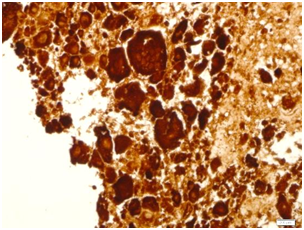

A specimen labeled as left frontoparietal hematoma - ? cavernoma from a 41 year old non-hypertensive female patient on ventilator was received for histopathologic examination. The patient was transferred from outside hospital to neurosurgical department of our hospital for craniotomy and evacuation of intracerebral hematoma. The clinoradiologic diagnosis was spontaneous intracerebral hematoma with intraventricular extension with normal ventricle, probably due to cavernoma. The microscopic examination of the specimen revealed extensive hemorrhage with peripherally placed mono-nucleated and multinucleated atypical cells. The mononucleotide cells were medium to large size with abundant cytoplasm and central large hyperchromatic nuclei. The multinucleated cells were large with abundant eosinophilic cytoplasm and hyperchromatic multinucleated bizarre nuclei. They were considered as cytotrophoblasts and syncytiotrophoblasts respectively (Figure 1-4). Immunohistochemistry showed that the atypical cells were CKAE1AE3 +, HCG+, GFAP-, CD31- and Vimentin- (Figure 5 to 10). A thin rim of GFAP positive glial tissue was seen in one fragment. Based on these findings, a diagnosis of metastatic choriocarcinoma was made. The patient survived the surgery and started recovering neurologically, but chose to go back to her own country for further management. So, we could not get any details of her obstetric history or previous medical illness.

Figure 4 Syncytiotophoblasts.

Figure 7 HCG.

Figure 8 HCG